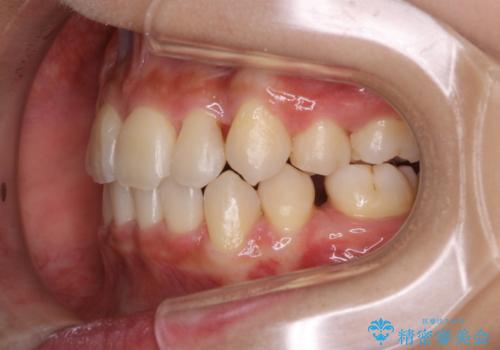

PMTC60分コースを行いました。紅茶による着色が全体的に付着していました。

インビザライン中の患者様で、紅茶を飲んだ後にそのままマウスピースをはめていたそうです。着色が、かなり目立っていた為、追加アライナーのタイミングで全体の着色を除去し、とても綺麗になりました。